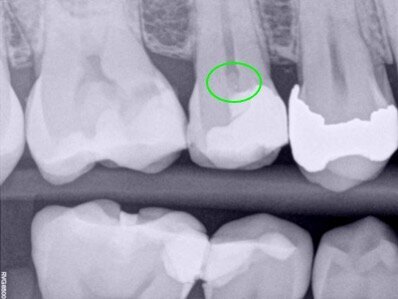

During an urgent appointment, a 35-year-old male patient reported sharp and short-lasting pain in tooth #15 in response to cold stimuli. The established diagnosis was reversible pulpitis and normal periapical tissue. During the removal of the old amalgam restoration, pulp exposure of approximately 3 mm in diameter was created at the level of the buccal pulp horn (Fig. 1a–g). As there was no profuse bleeding and the pulp diagnosis was reversible pulpitis, it was decided to proceed with a direct pulp capping procedure.

Fig. 1a–g: A direct pulp capping procedure sequence. Initial bitewing radiograph. The proximity of the previous restoration to the pulp space was evident (a). Initial periapical radiograph. No evidence of periapical disease (b). Pulp exposure (c). Pulp exposure after haemostasis, achieved after applying pressure with a sterile cotton pellet for 20 seconds (d). Placement of pulp capping material before removal of excess material in the peripheral areas (e). Non-radiopaque temporary restoration in place (f). Post-op radiograph taken at the end of the first appointment with the non-radiopaque temporary restoration in place (g).